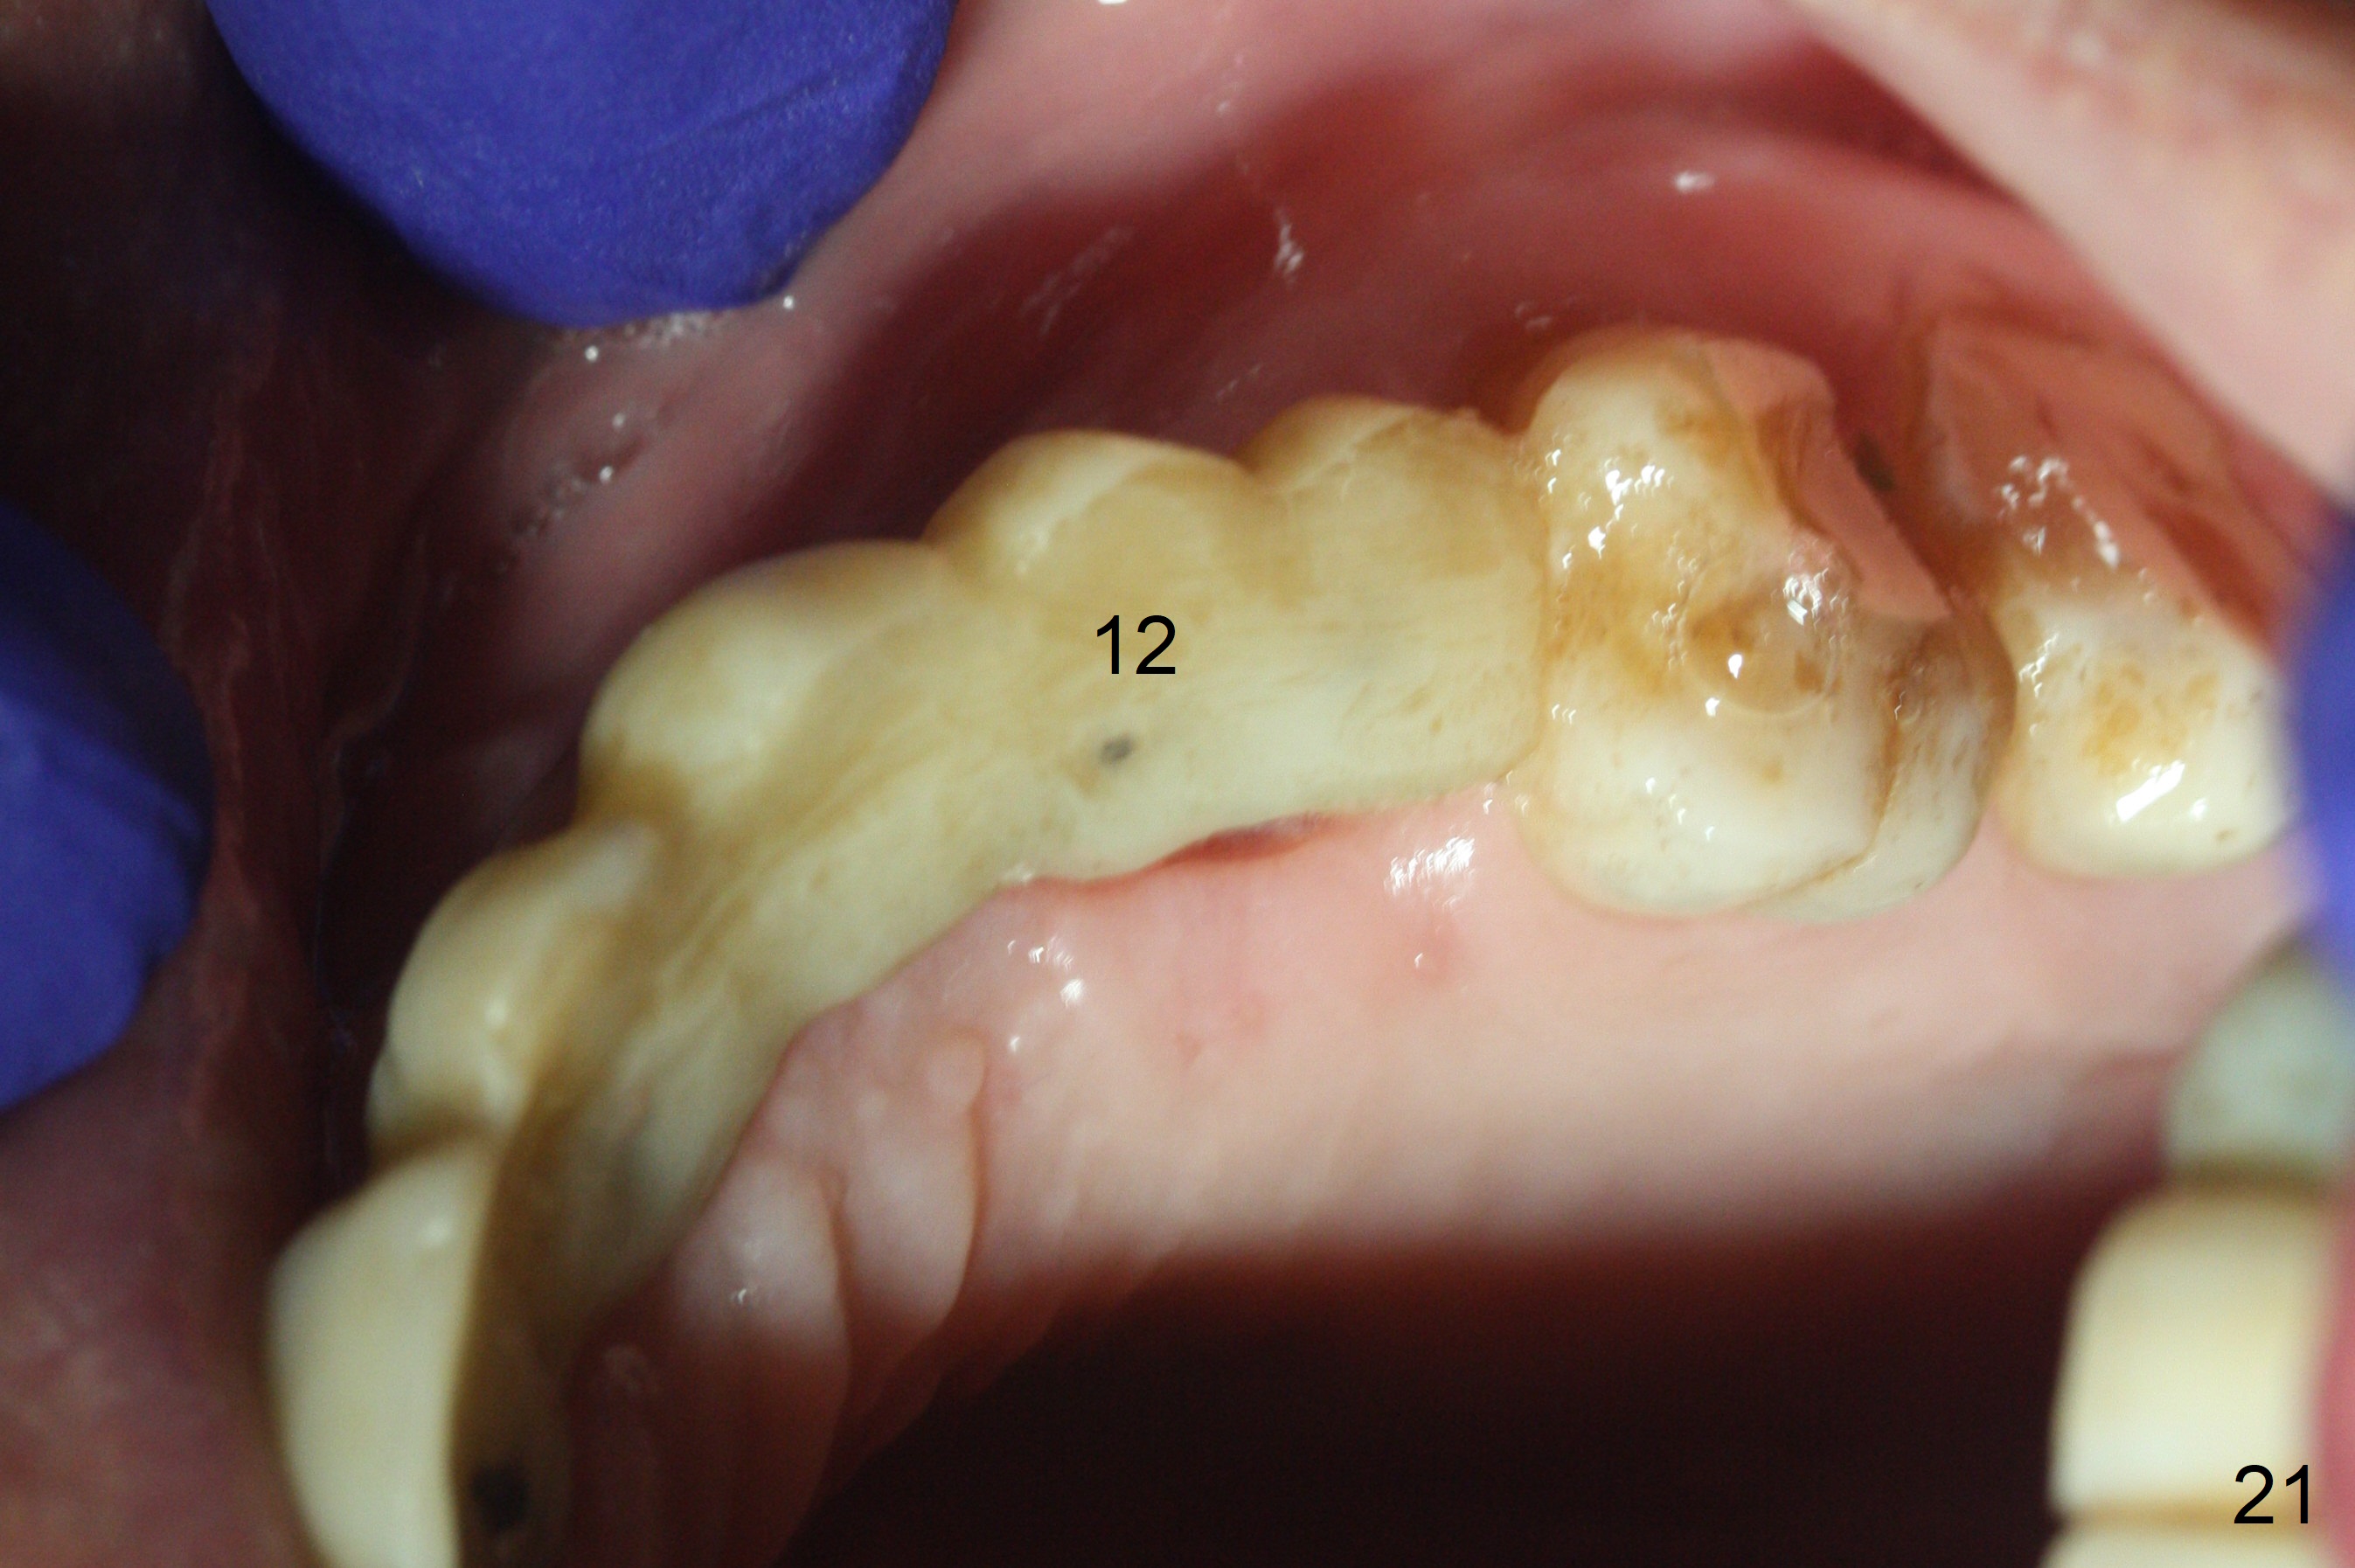

The soft tissue heals 2 weeks postop (Fig.21).